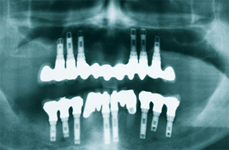

If you have all the teeth missing in your mouth, you have the options:

- Implant supported overdentures

- Implant supported full bridge

- Bone preservation: Implants supporting full bridges and dentures will replace some of your tooth roots, having a preservative action on jaw bone. With conventional dentures, the bone that previously surrounded the tooth roots begins to resorb (deteriorate). Dental implants integrate with your jawbone, helping to keep the bone healthy and intact.